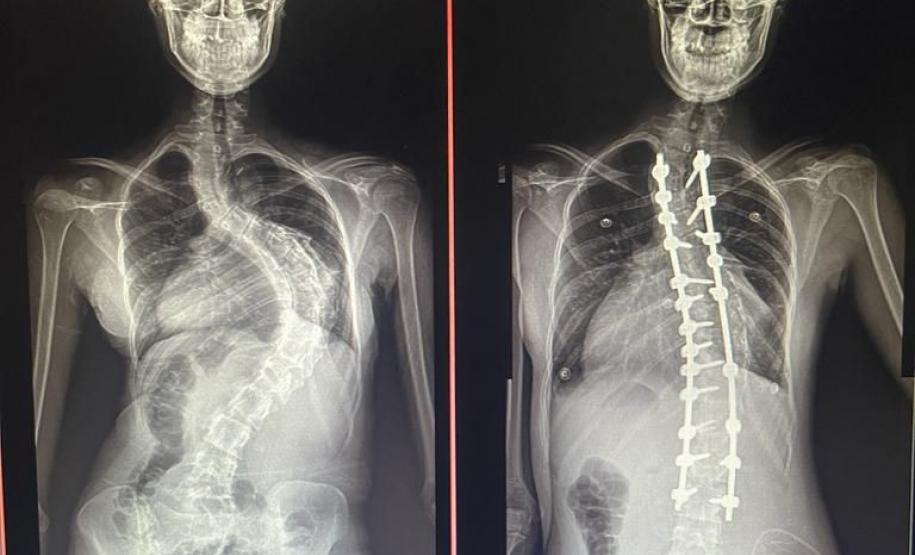

Aos 14 anos, a adolescente Milena de Andrade Carvalho, moradora de Guaratuba, no Litoral do Estado, foi diagnosticada com escoliose idiopática. Sem causa definida, esse tipo de escoliose pode surgir a partir dos quatro anos até a adolescência e ocorre durante o estirão de crescimento. Quando a condição da curvatura ultrapassa os 40 graus, a escoliose se torna progressiva e o paciente continua entortando. Essa condição ocorre com maior frequência em meninas e é muito importante que os pais estejam atentos a qualquer sinal do problema.

“Descobrimos a escoliose por acaso, nunca tínhamos percebido a deformidade, até que um dia ao amarrar meu biquíni, minha mãe observou que eu estava com a coluna torta e ao passar a mão percebeu a curvatura. Decidimos então procurar atendimento médico e tive o diagnóstico da doença já com 50 graus de curvatura e indicação imediata de cirurgia”, contou a adolescente.